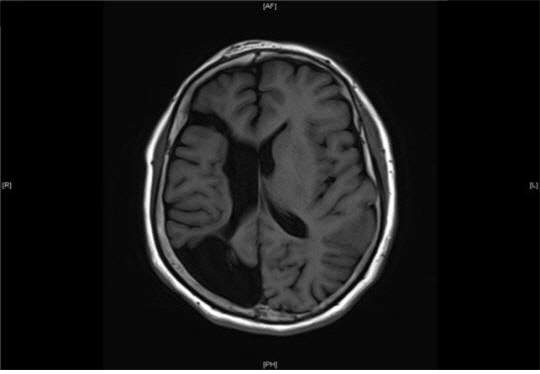

중풍은 뇌로 가는 혈액 흐름에 문제가 생겨 뇌 기능에 변화가 나타나는 상태를 말합니다. 뇌는 산소와 영양분을 지속적으로 공급받아야 정상적으로 작동하는데, 혈액이 제때 전달되지 않거나 흐름이 막히면 해당 부위의 기능에 이상이 생길 수 있습니다. 이때 나타나는 변화가 중풍으로 불립니다. 우리나라에서는 흔히 중풍이라는 표현을 사용하며, 의학적으로는 뇌졸중이라는 용어로도 알려져 있습니다.

중풍은 갑작스럽게 나타나는 경우가 많아 평소와 다른 신체 변화를 빠르게 인식하는 것이 중요합니다. 얼굴 움직임이나 말하는 능력, 팔다리의 힘, 시야 인식 등 여러 기능에서 변화가 감지될 수 있습니다. 증상은 뇌의 어느 부위에 문제가 생겼는지에 따라 다르게 나타납니다. 일부 경우에는 짧은 시간 동안 나타났다가 사라지기도 하지만, 이는 몸이 보내는 중요한 신호로 받아들이는 것이 필요합니다.

중풍은 나이 증가와 함께 발생 가능성이 높아질 수 있으며, 평소 혈압이나 혈관 상태와도 연관이 있습니다. 따라서 중풍은 갑작스러운 마비나 의식 변화만을 의미하는 것이 아니라, 뇌 기능 전반에 영향을 줄 수 있는 상태로 이해하시는 것이 바람직합니다.